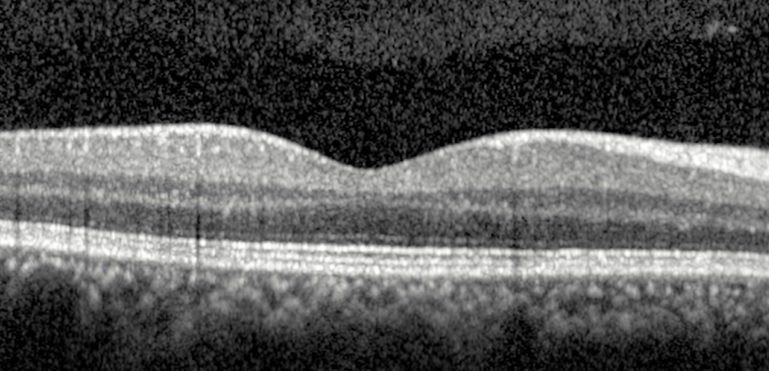

Quais estruturas podemos identificar num exame de OCT sem alterações?

Quais doenças da Interface Vitreorretiniana estão evidenciadas nas imagens abaixo?

Quais os principais achados nos exames abaixo?